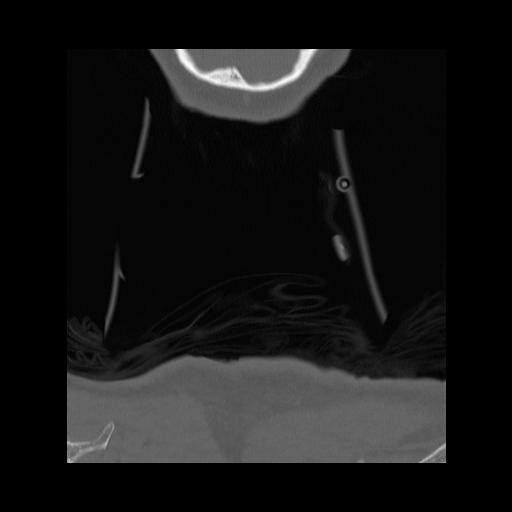

16 HUESO,,Coronal,2.000,HUESO,Coronal,